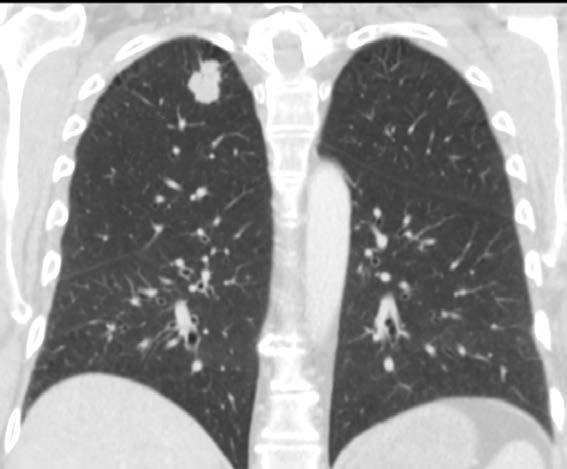

Mynd 6-1 Lítið lungnakrabbamein í hægra lunga (ör) sem fannst við skimun með tölvusneiðmyndum.

Með tilkomu tölvusneiðmyndatækni (TS) varð unnt að finna mun smærri hnúta í lungum en áður var mögulegt með hefðbundnum röntgenmyndum (mynd 6-1). Á síðustu áratugum hefur verið efnt til stórra framvirkra samstarfsverkefna, bæði í Bandaríkjunum og Evrópu. Fyrstu rannsóknir á skimun með TS voru gerðar í Japan og fyrsta alþjóðlega rannsóknin benti til þess að unnt væri að finna um

Þar var 53 þúsund reykingamönnum/konum skipt í tvo slembihópa þar sem annar hópurinn hlaut árlega skimun með TS og hinn með röntgenmyndum. Niðurstöður voru birtar 2011 og sýndi rannsóknin 20,4% lækkun dánartíðni vegna lungnakrabbameins í TS hópnum (p<0.004).1 Auk þess lækkaði dánartíðni í skimunarhópnum í heild um 6,7% (p<0.02). Þetta var besti árangur sem náðst hafði með skimun og vakti vonir um að loksins væri komin aðferð til að lækka umtalsvert dánartíðni þessa snúna sjúkdóms. Skimunarrannsóknir með TS hafa einnig farið fram í Evrópu. Stærst þeirra er hollensk­belgíska NELSON rannsóknin þar sem 15,822 þátttakendum var skipt í skimunarhóp með TS sem fylgt var eftir í 6,5, ár og viðmiðunarhóp án skimunar. Niðurstöður NELSON rannsóknarinnar sýndu marktæka lækkun á dánartíðni, sem er meiri hjá konum en körlum, eða 36% lækkun borið saman við 26% hjá körlum.4,5